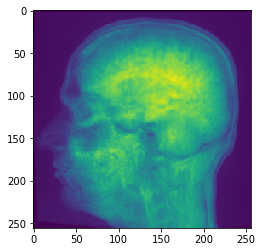

Copiar Corte#

Para visualizar cortes específicos sin que la imagen salga de la memoria de la GPU, utilice el método copy_slice.

# Copiar Corte

image_slice = cle.create([256, 256]);

slice_z_position = 40.0;

cle.copy_slice(input_image, image_slice, slice_z_position)

# mostrar resultado

cle.imshow(image_slice)